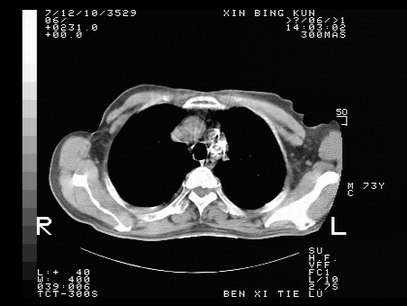

标题: CT10820:男,73岁,病史肺TB,现病史肺炎,直肠CA术后 [打印本页]

双肺间质改变,依据病史双肺多发结节灶考虑转移,少量胸水.

1.两肺结核.2.两肺多发转移瘤.3右侧少量胸腔积液4.主动脉钙化.

双肺多发结节及条片状致密影,右侧少量胸腔积液。临床:直肠ca术后,肺tb病史。综合考虑:1 双肺转移!2 继发性肺结核合并感染!

此人病史较复杂,原有肺结核,直肠癌术后。肺部病灶形态亦呈多形性。因此,不可仅以一种病来解释肺部的病变。双肺多发的类圆形结节灶,结合病史还是首先考虑转移瘤,而双肺其余病灶还需结合化验室检查,结核或肺部感染在无其它检查资料的情况下不好排除。还是那句话----放射科医生不是开照像馆的,我们也是医生,看片一定要多结合临床及其它检查资料。要当一名合格的放射科医生,并不比当一名临床医生容易,我们可别把自已不当医生看。

两肺多发结节影,并见滋养动脉与其相连,考虑 两肺转移. 右侧胸腔积液考虑胸膜转移.

左肺上叶下叶背段,右肺中下叶见多发斑片状、条索状高密度影,兵变周围小结节影形成“树芽”样改变。 左肺上叶舌段近前胸壁处及右肺中叶内侧段见结节影。右侧胸膜腔内见液体密度区。纵隔内未见明确增大淋巴结。考虑左肺上叶舌段近前胸壁处及右肺中叶转移瘤可能性大。两肺继发型肺结核。右侧胸腔积液。